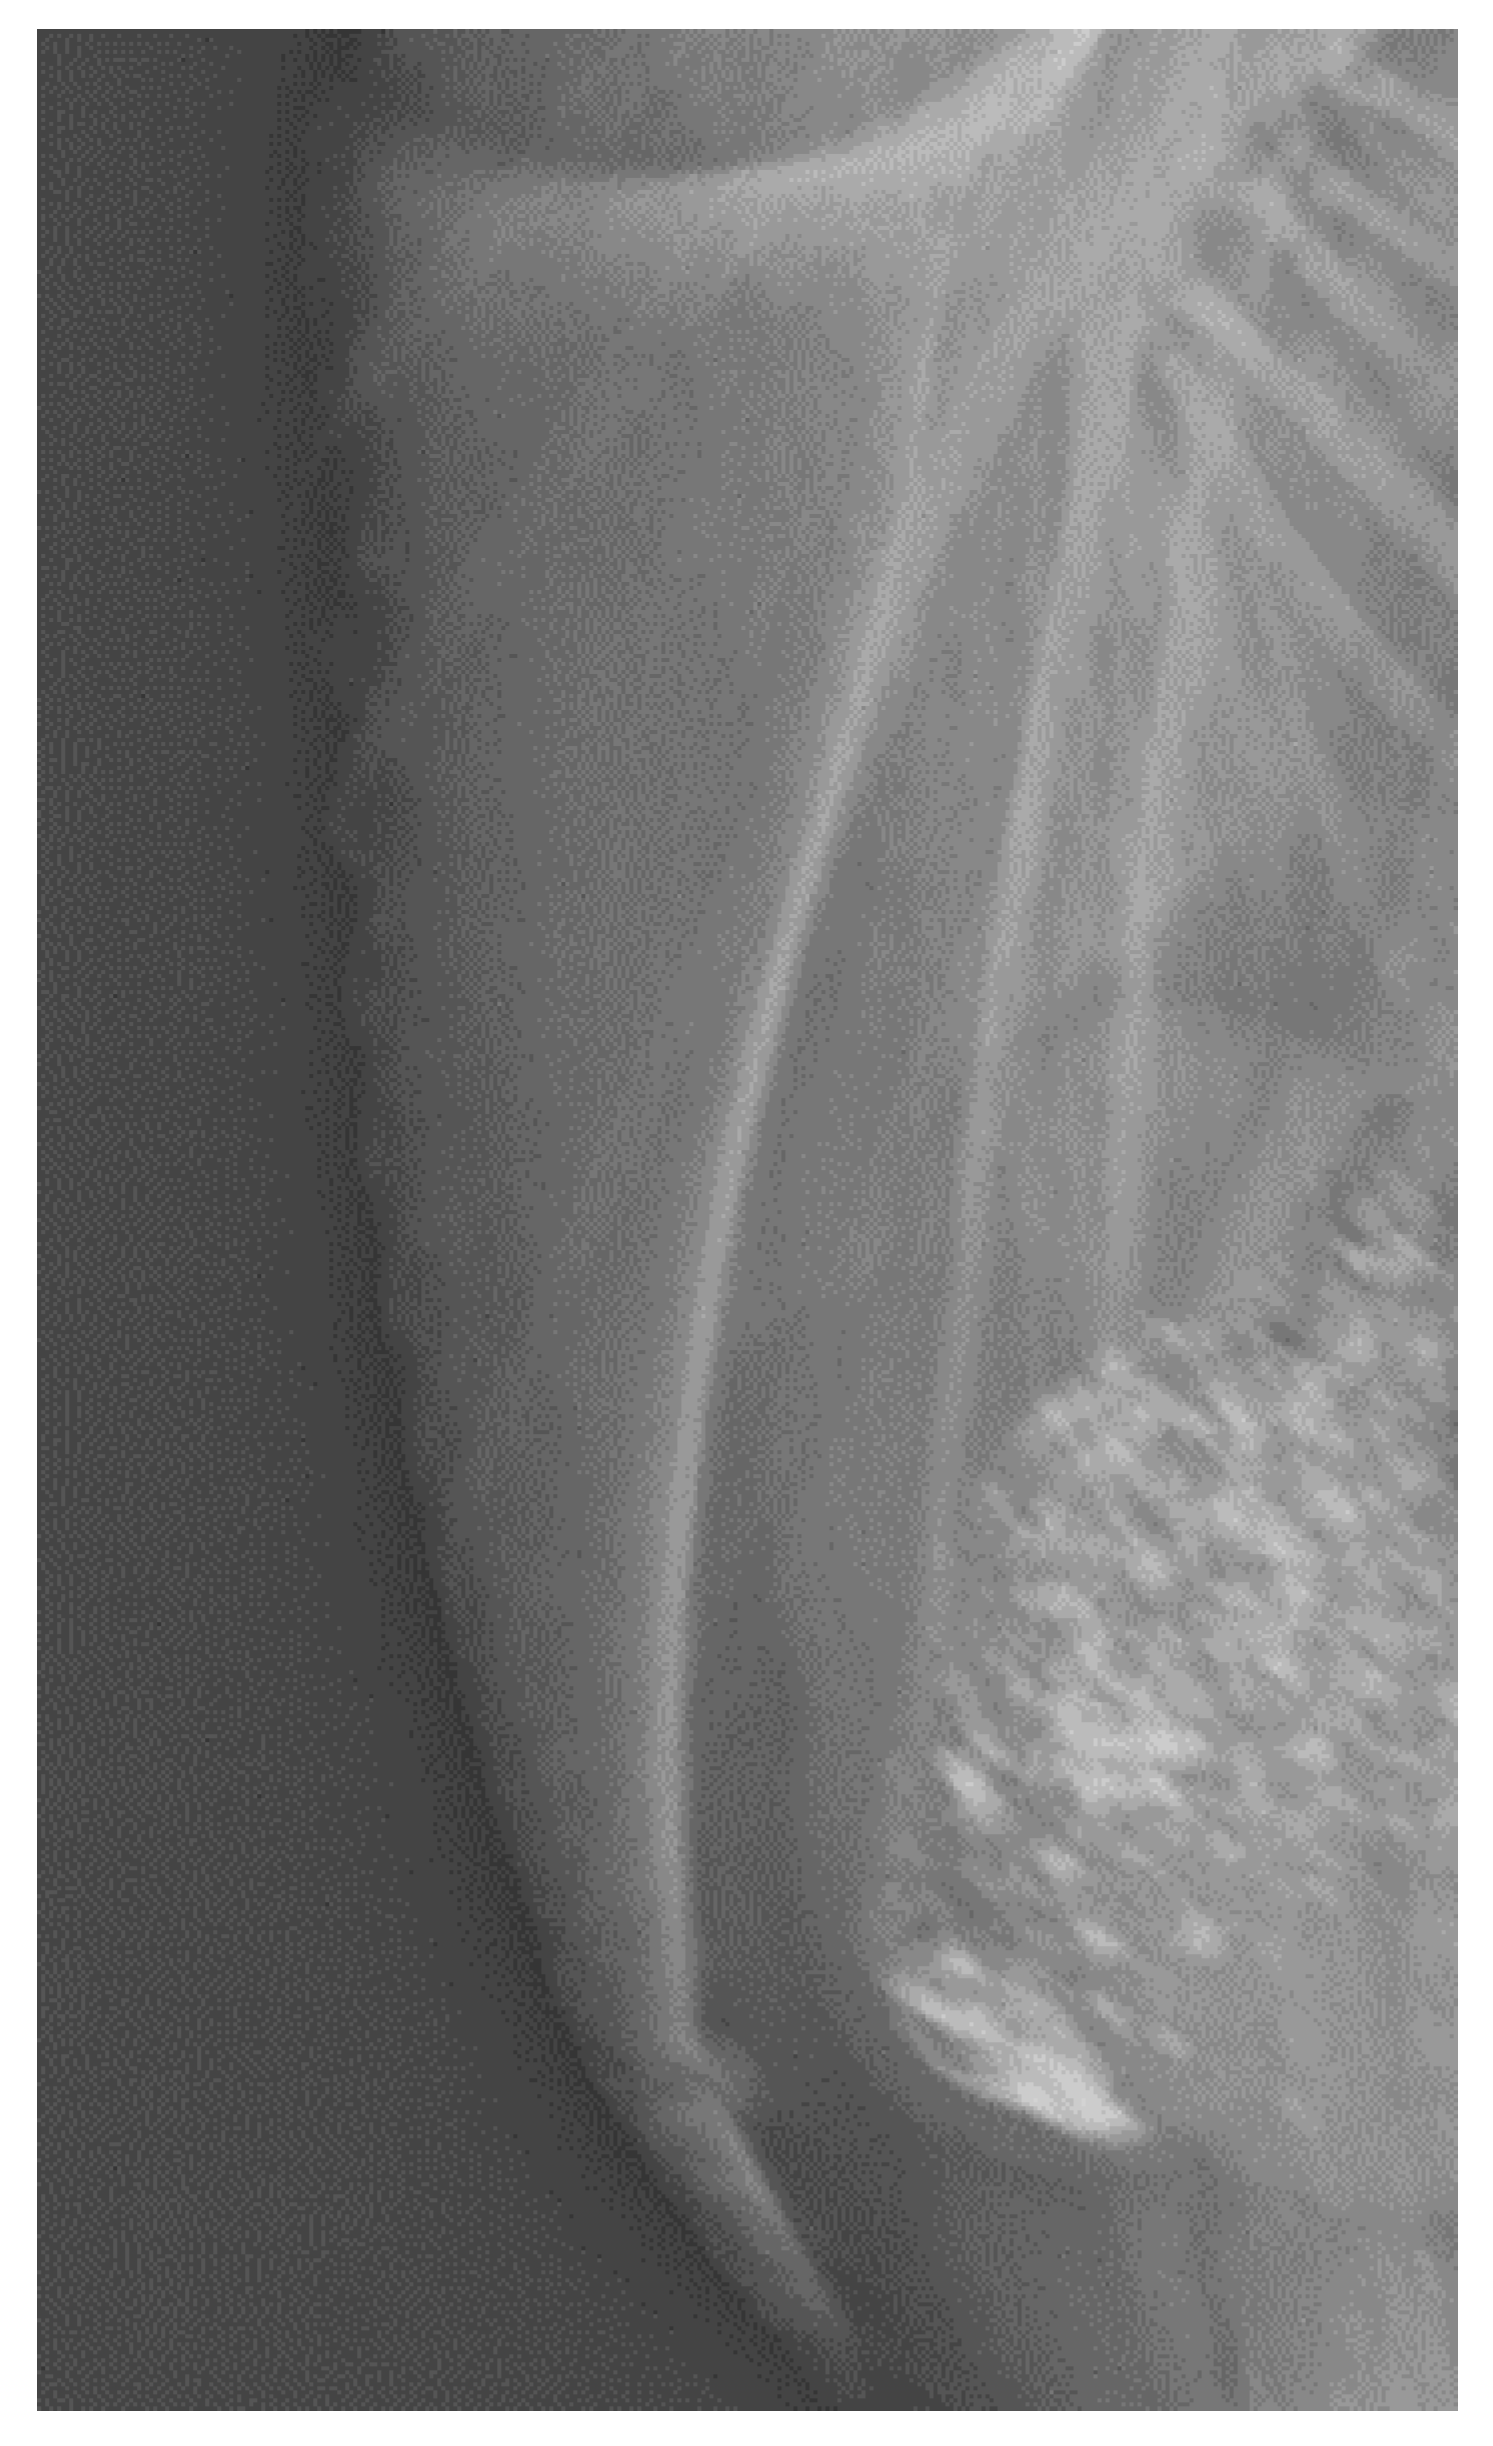

- Baur, S.; Rufener, C.; Toscano, M.J.; Geissbühler, U. Radiographic evaluation of keel bone damage in laying hens—morphologic and temporal observations in a longitudinal study. Front. Vet. Sci. 2020, 7, 7. [Google Scholar] [CrossRef] [PubMed]

- Rufener, C.; Baur, S.; Stratmann, A.; Toscano, M.J. A reliable method to assess keel bone fractures in laying hens from radiographs using a tagged visual analogue scale. Front. Vet. Sci. 2018, 5, 124. [Google Scholar] [CrossRef]